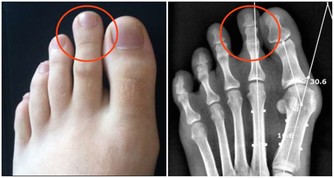

麻疹是一種由麻疹病毒(Measles virus)引起的高度傳染性疾病,主要通過空氣中的飛沫傳播。麻疹的症狀包括:

麻疹可能引發嚴重的併發症,如肺炎、腦炎,甚至死亡。未接種疫苗者在接觸麻疹患者後,約90%會感染,顯示出病毒的高傳染性。